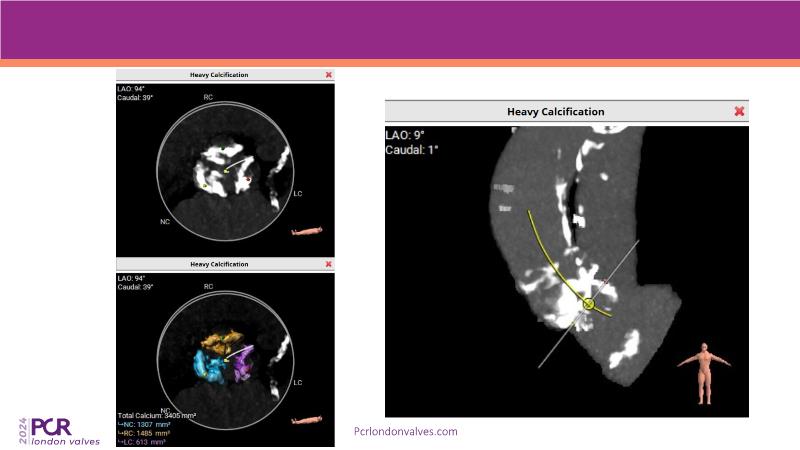

Watch this session to explore expert insights into best-in-class TAVI practices, from pre-procedural imaging and treatment strategy to procedural tips and post-procedural management. Learn from a compelling case study of an 88-year-old male patient with severe symptomatic aortic stenosis treated with the innovative MyVal Octapro THV. Discover key findings from the Landmark RCT sub-group analysis and delve into the unique scientific and design philosophy of MyVal Octapro, along with its real-world clinical potential.

- To learn from the experts best-in-the-class TAVI practice: pre-procedural (Imaging, sizing rationale, treatment strategy), procedural tips and tricks and post-procedural management